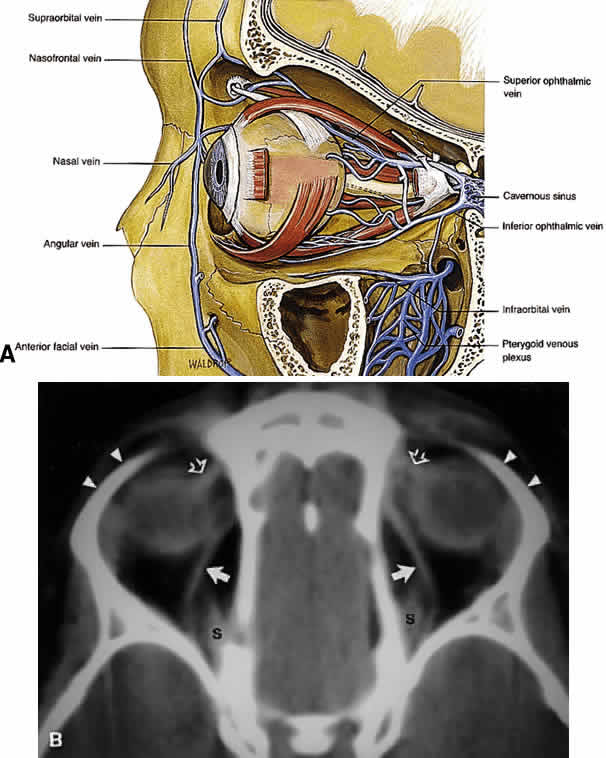

plexus.  Fig. 21. A. Venous drainage of the orbit. Major drainage is supplied by the superior

ophthalmic vein, which drains into the CS. Note that the central retinal

vein usually drains directly into the CS. Drainage through the pterygoid

plexus is minor under normal conditions but becomes very important

during outflow problems through the CS (carotid-cavernous or dural-cavernous

fistulas). B. Axial CT reveals the course of the superior ophthalmic veins (closed arrows) beneath the superior rectus muscles (S). Also imaged are the superior

orbital rims (arrowheads) and the superior oblique muscles (open arrows) as each passes through the trochlea. (A from Dutton JJ: Atlas of Clinical and Surgical Orbital Anatomy, p 79. Philadelphia, WB

Saunders, 1994) Fig. 21. A. Venous drainage of the orbit. Major drainage is supplied by the superior

ophthalmic vein, which drains into the CS. Note that the central retinal

vein usually drains directly into the CS. Drainage through the pterygoid

plexus is minor under normal conditions but becomes very important

during outflow problems through the CS (carotid-cavernous or dural-cavernous

fistulas). B. Axial CT reveals the course of the superior ophthalmic veins (closed arrows) beneath the superior rectus muscles (S). Also imaged are the superior

orbital rims (arrowheads) and the superior oblique muscles (open arrows) as each passes through the trochlea. (A from Dutton JJ: Atlas of Clinical and Surgical Orbital Anatomy, p 79. Philadelphia, WB

Saunders, 1994)